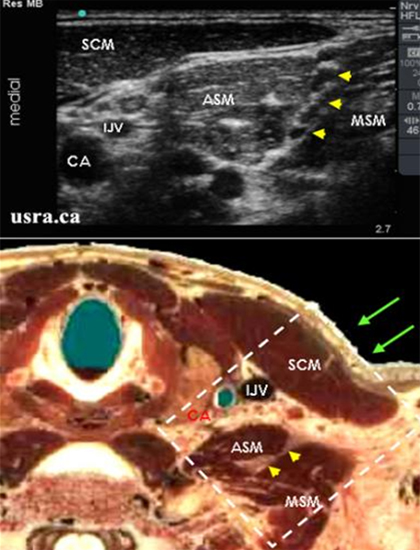

例如,在进行肌间沟臂丛神经阻滞的时候,我们会去识别前斜角肌,中斜角